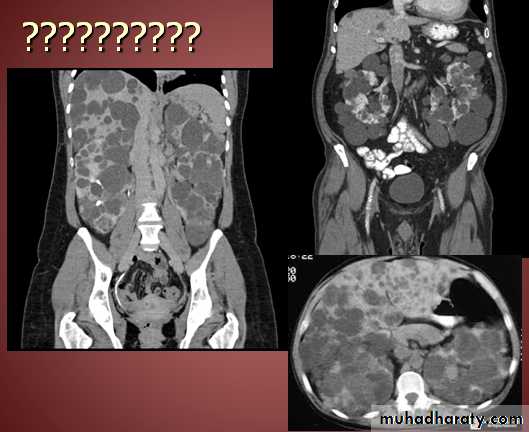

CT abdomen

Hydatid cyst

Appear as large oval hypo dense area density of fluid with well defined margin , sometime at their periphery multiple flecks of calcification are seen at their periphery .

Hydatid cyst with daughter cyst , appear as multiple hypo densities rounded area within the main loculi with multiple rim of

calcification

Hydatid cyst within the liver

CT Scane